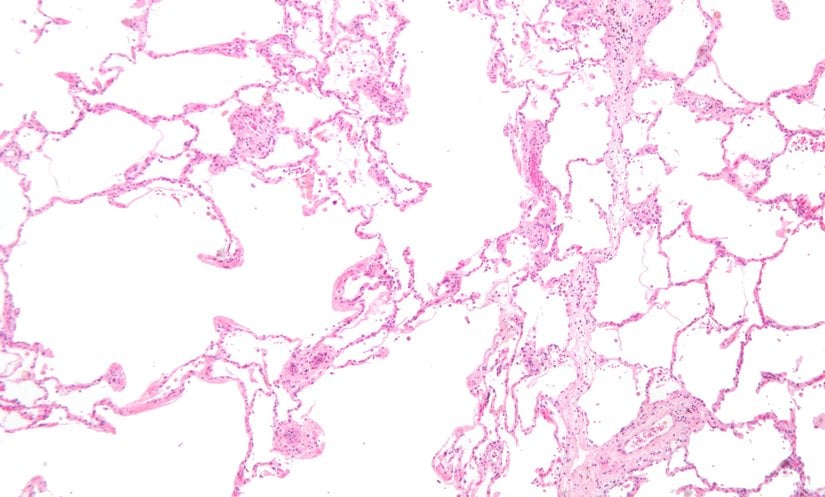

Resmin solunda şiddetli amfizem (büyük boş alanlar) görülmektedir. Görüntünün sağındaki akciğer dokusu alveollerin göreceli olarak korunmasına sahiptir. Görüntünün üst kısmı plevral (göğüs boşluğunu içten kaplayan ve akciğerleri çevreleyen, iki katlı, ince bir zar tabakası) yüzeye çok yakındır.